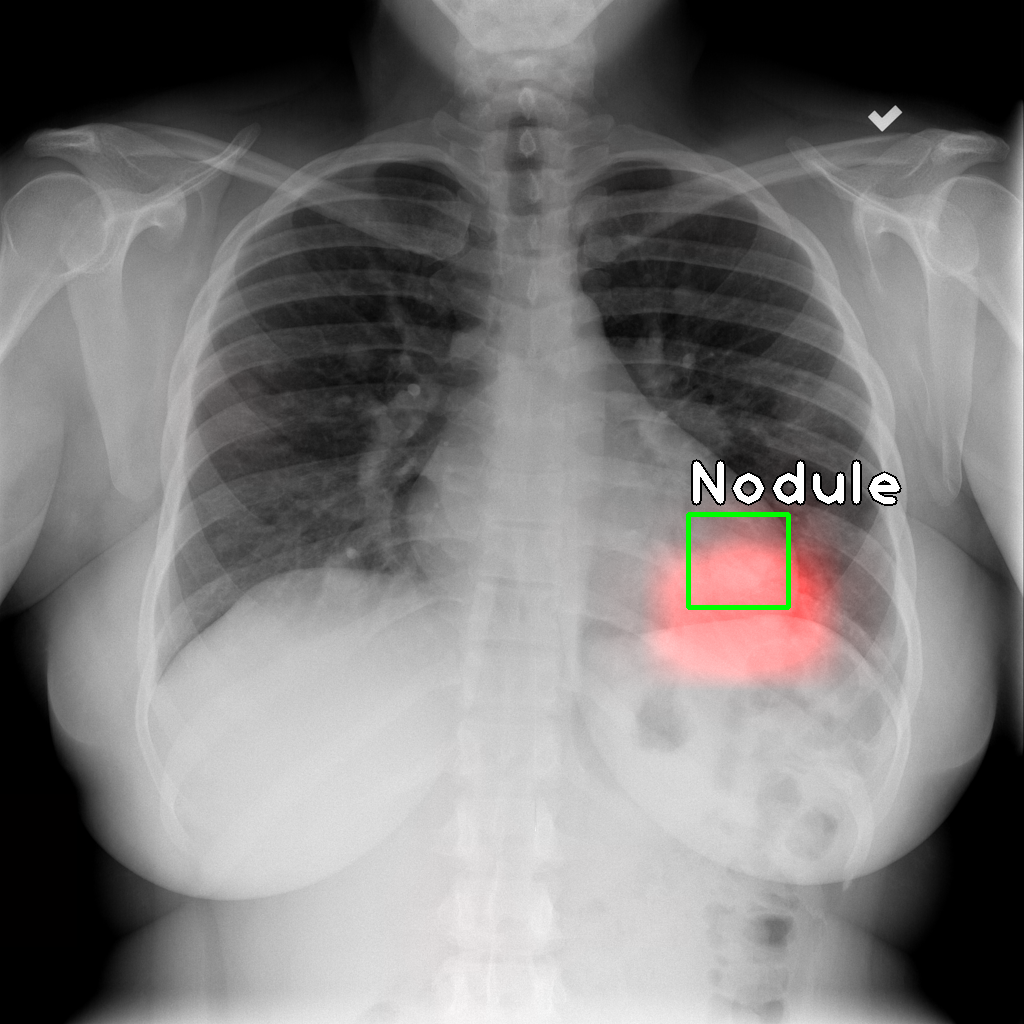

We note that the IoR data is fairly similar to the IoU data, and most of the observations above hold in this case as well. Qualitative examples of the localizations derived are shown in Figure 1.